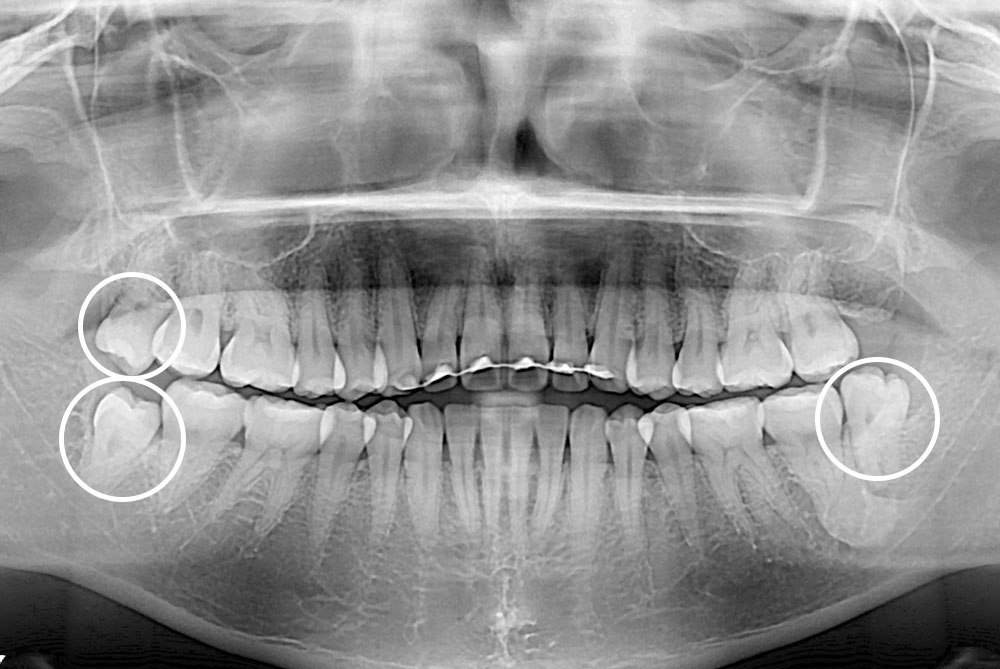

[사랑니] 매복 사랑니 발치

치료후 : 2019-05-21

세종치과는 구강악안면외과학 박사이신 원장님이 발치하는 치과입니다.